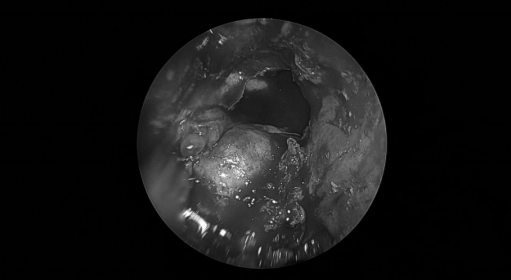

手术经过

术后病理:(颅底肿瘤)表皮样囊肿。(双侧鼻息肉) 息肉,嗜酸性粒细胞浸润<10% 背景炎细胞。

术后诊断:右侧鞍旁、中颅窝底良性肿瘤(表皮样囊肿),右侧分泌性中耳炎,双侧鼻息肉,慢性鼻窦炎